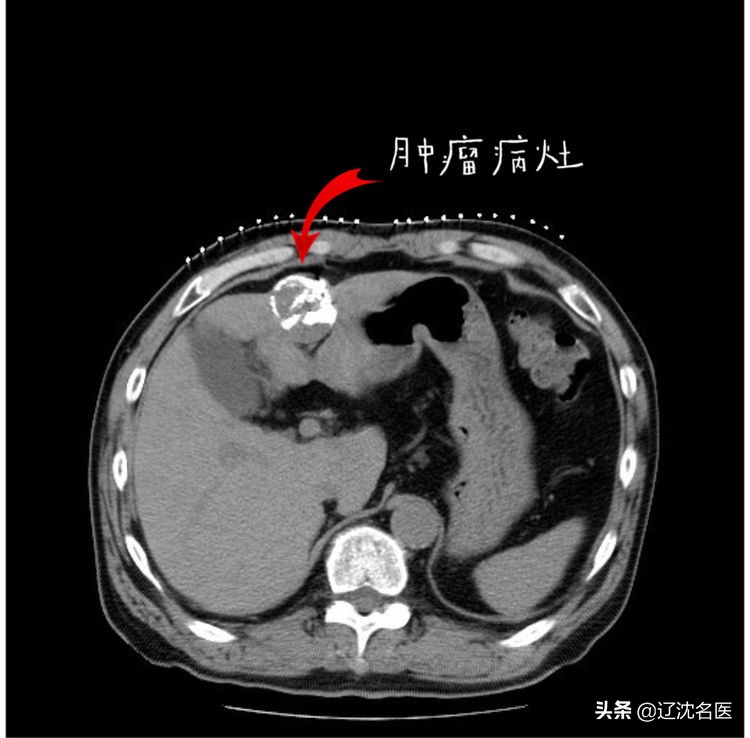

粒子植入术中定位

粒子植入手术术中穿刺